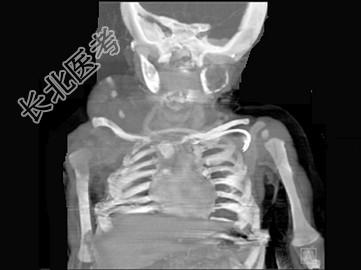

- 单项选择题男,2岁, 左侧颜面部、右肩部肿块,疼痛, 结合图像,最可能的诊断是 ( )

A、骨结核

B、骨髓炎

C、骨嗜酸性肉芽肿

D、骨囊肿

E、骨肉瘤